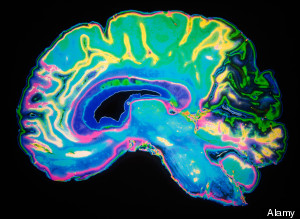

We can guess what our brains go through while we're dancing; we experience euphoria, elation, happiness, and probably nervousness for those with two left feet. While we're just conjecturing, scientists at Bangor University are discovering precisely what goes through the brain while we're shaking our groove thing. Dr. Emily Cross enlisted the help of contemporary dancer Riley Watts to examine how the brain responds to movement, both choreographed and improvised.

The contemporary dancer boogied in a variety of settings, including a 3D motion capture studio, and then had an MRI exam while he watched videos of himself. His brain's reactions were then recorded, giving us a window into the inner workings of our mind. Cross' focus is on the relatively new field of neuroaesthetics -- a field where the brain's reactions to artistic endeavors is studied -- creating the perfect opportunity to collaborate with Watts, who was thrilled to participate.